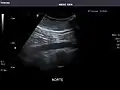

Kidneys: Right and left kidneys measure 11.5 cm and 12 cm in length respectively. No hydronephrosis. Small left lower pole kidney cyst.

Right kidney